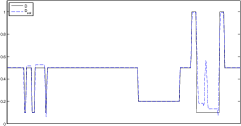

The data (see Figures 1 and 2) was generated in the diffusion model (1.2) using self-written (linear-basis) finite element code in MATLAB. For both examples, we took and used a uniform boundary condition . The simulated data were generated on a -grid and then down-sampled (by averaging) to to avoid inverse crime. After that, Gaussian noise with different intensities (standard deviations of and of the average signal value ) was added to the data.

Reconstruction results and error profiles at different noise levels can be seen in Figures 3 and 4. In both examples, the noise-free reconstructions are very accurate and contain mostly smoothing error. In the low-noise reconstructions, due to the fact that more regularization is necessary, some of the parameter variation is underestimated. In the high-noise examples, most detail in is lost since a lot of regularization is required to get reasonable results. The fine detail in can, however, still be recovered very accurately in both examples.